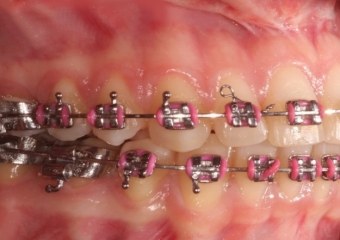

Mordida inicial